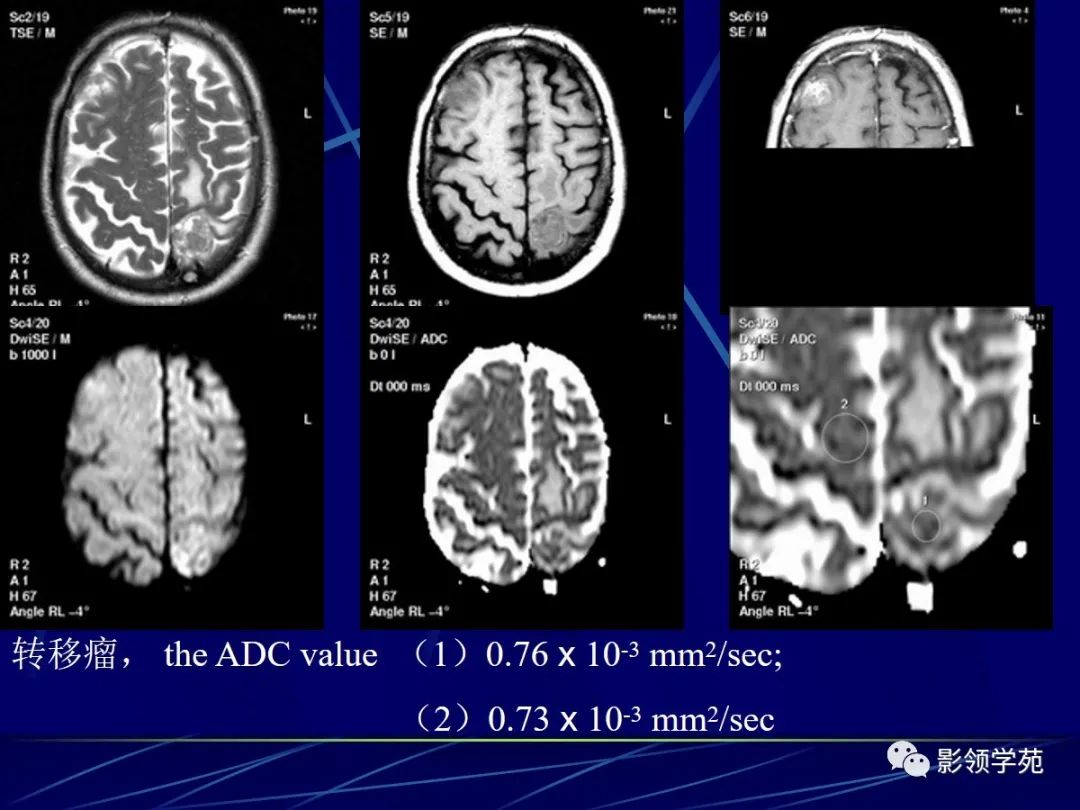

转移瘤

据报道转移瘤在DWI上呈等或稍高信号,而其ADC值范围约为0.82–1.24 x 10-3 mm2/sec 。

转移瘤的非坏死部分在DWI上信号多变 (通常为 iso-或 hypointense; 偶尔呈 hyperintense)。转移瘤的坏死部分在DWI上为显著低信号,ADC值明显升高。